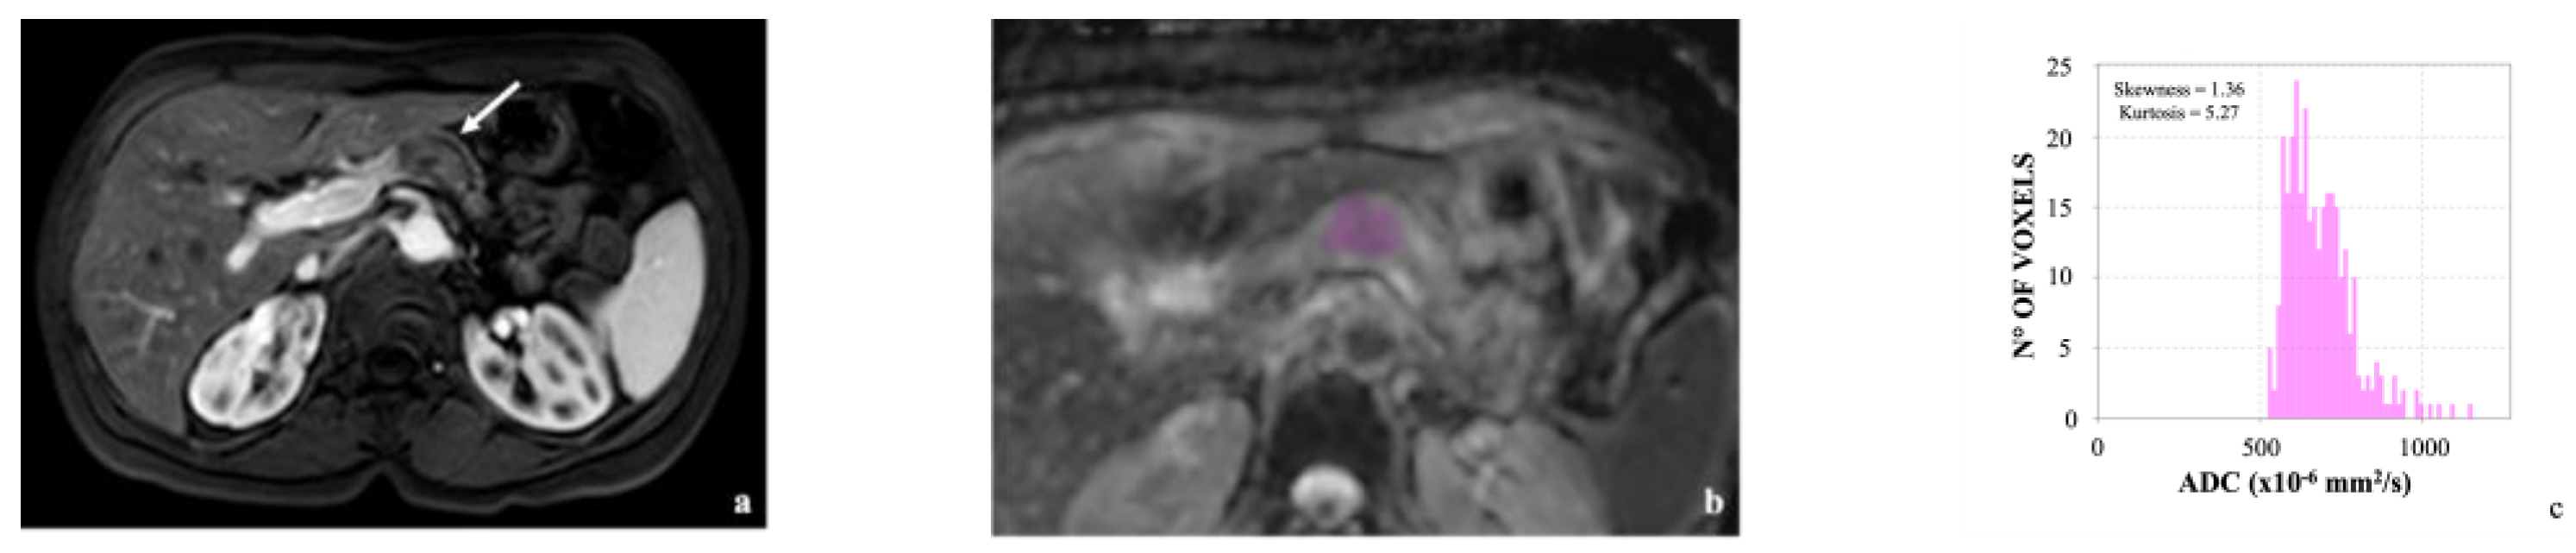

3.2. Image Analysis

- De Robertis, R.; Beleù, A.; Cardobi, N.; Frigerio, I.; Ortolani, S.; Gobbo, S.; Maris, B.; Melisi, D.; Montemezzi, S.; D’Onofrio, M. Correlation of MR Features and Histogram-Derived Parameters with Aggressiveness and Outcomes after Resection in Pancreatic Ductal Adenocarcinoma. Abdom. Radiol. 2020, 45, 3809–3818. [Google Scholar] [CrossRef]

| Skewness | 0.6 (−0.6;3.3) | 0.2 (−1.2;1.8) | 0.005 |

| Kurtosis | 4.3 (1.7; 17.3) | 3.8 (2.1; 11.1) | 0.032 |